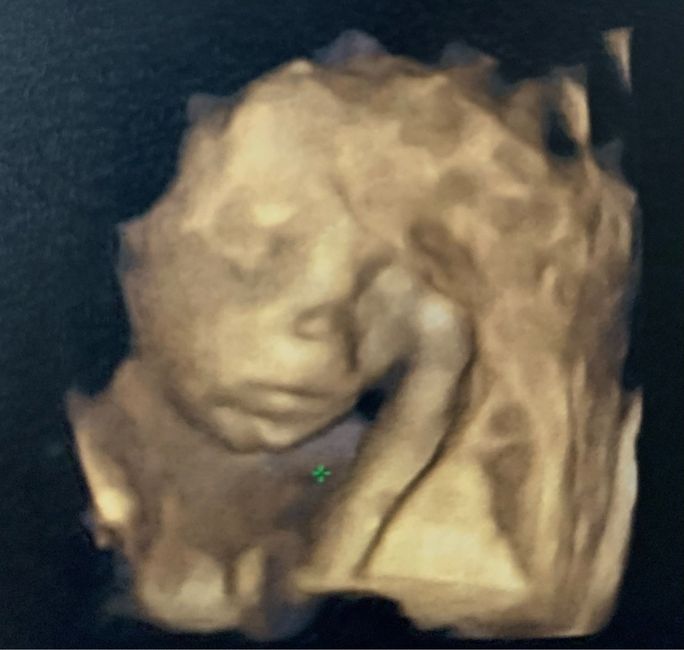

Future mamme Maggio 2023Da Tata , Il 12 Gennaio 2023 alle 22:51

Ciao a tutte le future mamme ❤️ creo questo post per tutte le ragazze con DPP a Maggio 2023, visto che non l'ha ancora aperto nessuno! La DPP è prevista per il...